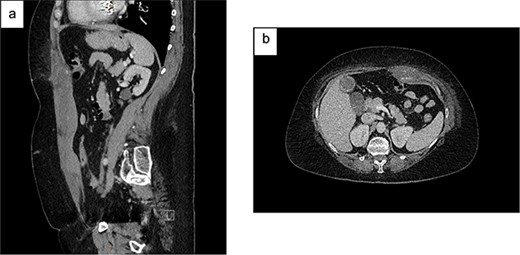

On Day 2, she became haemodynamically unstable with heart rate 150 bpm, systolic blood pressure 84 mmHg and a haemoglobin drop to 84 g/L. She was given oral Vitamin K and transfused packed red blood cells (PRBC) and fresh frozen plasma. CT angiography showed an increased RSH (61x36x301mm) with multiple foci of arterial enhancement, and a large pelvic extraperitoneal haematoma (119x81x121mm) displacing the urinary bladder posteriorly with active extravasation posterior to the left superior pubic ramus (Fig. 2). The Surgical team held extensive discussions with Interventional Radiology, Intensive Care, Haematology, Cardiology and Urology. The balance was in favour of ongoing conservative management due to (i) the thrombosis risk associated with discontinuing anticoagulation and (ii) the technical difficulty and risks of embolisation in an anticoagulated patient with multiple foci of arterial extravasation.

CT angiography (portal venous phase): (a) increased size of RSH and ongoing active extravasation – sagittal (top) and axial (bottom) views. (b) Extraperitoneal haematoma compressing and displacing urinary bladder – sagittal (top) and axial (bottom) views.